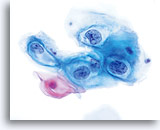

En raison de leur morphologie, les cellules issues de lésions de bas grade comptent parmi les anomalies intra-épithéliales les plus faciles à localiser et à identifier. En comparaison, les noyaux LSIL sont les plus grands et présentent un rapport N/C inférieur aux HSIL ou carcinomes. Ces cellules affichent une atypie nucléaire plus importante que les ASCUS (ce qui se traduit par une augmentation de la taille nucléaire, une irrégularité de la chromatine et une irrégularité de l’enveloppe nucléaire). Les noyaux peuvent occasionnellement ne pas être aussi hyperchromatiques que sur les frottis conventionnels, mais ils le sont toujours par rapport aux cellules normales environnantes. Les changements associés au HPV (par exemple, formation de cavités dans le cytoplasme) sont plus évidents grâce à la fixation liquide et à la technique de transfert, ce qui élimine la déformation des cellules associée à la méthode d’étalement conventionnelle. La méthode ThinPrep préserve mieux ces changements cellulaires, ce qui permet une meilleure distinction entre les véritables cavités cytoplasmiques induites par le HPV et les vacuoles bénignes/dégénératives et/ou les cellules malpighiennes glycogénées.

Comme il s’agit de cellules malpighiennes matures, elles gardent leur forme polygonale et conservent en partie leur taille normale. La taille des noyaux est au moins 3 à 4 fois supérieure à celle d’une cellule intermédiaire normale. En revanche, quand les changements associés au HPV sont évidents, les cellules peuvent être plus petites (quasiment parakératosiques), tout comme les noyaux (quelque peu pycnotiques) qui présentent en outre une binucléation et/ou multinucléation. Ces noyaux pycnotiques affichent en outre des caractéristiques anormales : hyperchromasie, augmentation de la taille par rapport à une cellule malpighienne superficielle normale, légère variation de la forme et de la taille, etc. Il est important d’insister sur le fait qu’une interprétation de LSIL/HPV implique des cavités cytoplasmiques nettes accompagnées de la morphologie nucléaire anormale décrite ci-dessus.